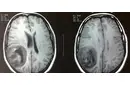

Bebeklerde beyin kistleri, genellikle doğumdan önce veya doğum sırasında oluşabilen sıvı dolu keseciklerdir. Bu kistler, beyin dokusunda veya çevresinde yer alabilir ve çoğu zaman zararsızdır. Ancak bazı durumlarda, beyin kistleri beyin fonksiyonlarını etkileyebilir ve tedavi gerektirebilir. Bu makalede, bebeklerde beyin kistlerinin belirtileri, tanısı ve tedavi yöntemleri hakkında detaylı bilgi verilecektir. Bebeklerde Beyinde Kist Belirtileri Bebeklerde beyin kistlerinin belirtileri genellikle kistin boyutuna, konumuna ve etkilerine bağlıdır. Belirtiler şunları içerebilir:

Bu belirtiler, kistin beyin üzerindeki etkilerine bağlı olarak değişiklik gösterebilir. Dolayısıyla, ebeveynlerin bebeklerinde bu tür belirtiler gözlemlemesi durumunda hızlı bir tıbbi yardım alması önemlidir. Bebeklerde Beyin Kistlerinin Tanısı Bebeklerde beyin kistlerinin tanısı genellikle aşağıdaki yöntemlerle yapılır:

Bu tanı süreçleri, doktorun kistin doğasını anlamasına ve uygun tedavi yöntemini belirlemesine yardımcı olur. Bebeklerde Beyin Kistlerinin Tedavisi Bebeklerde beyin kistlerinin tedavisi, kistin türüne, boyutuna ve bebeğin genel sağlık durumuna bağlı olarak değişiklik göstermektedir. Tedavi seçenekleri şunlardır:

Tedavi süreci, her hasta için özeldir ve doktor tarafından titizlikle planlanmalıdır. Sonuç Bebeklerde beyin kistleri, çoğu zaman zararsız olsalar da, bazı durumlarda ciddi sağlık sorunlarına yol açabilir. Ebeveynlerin bebeklerinde herhangi bir belirti gözlemlediklerinde derhal tıbbi yardım almaları önerilmektedir. Erken tanı ve tedavi, bebeklerin sağlıklı gelişimi için kritik öneme sahiptir. Ekstra Bilgiler Bebeklerde beyin kistlerinin oluşumunda genetik faktörler, doğumsal anomali ve enfeksiyonlar etkili olabilir. Ebeveynlerin düzenli doktor kontrolü ile bebeklerinin sağlık durumunu takip etmeleri, olası sorunların önüne geçilmesine yardımcı olabilir. Ayrıca, bebeklerde beyin kistlerine dair farkındalığın artırılması, erken tanı ve tedavi süreçlerinin hızlanmasına katkıda bulunabilir. |